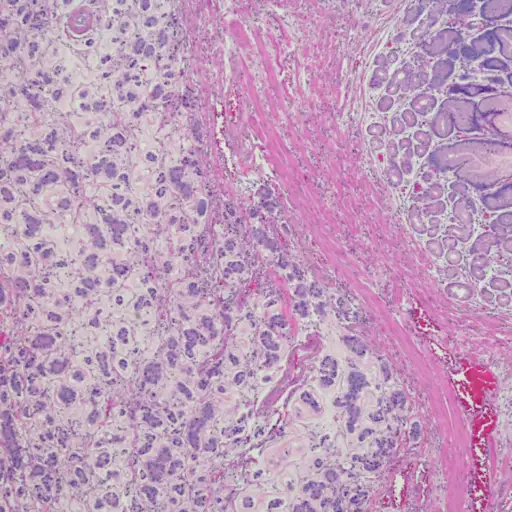

当异常细胞在胃粘膜形成和繁殖时,就会发生胃癌。大多数的胃癌症腺癌开始于器官最内层的粘膜层。根据纽约纪念斯隆凯特琳癌症中心的研究,发生在胃里的其他类型的癌症包括胃肠道间质瘤(始于胃部肌肉)、类癌(始于胃部分泌激素的细胞)和淋巴瘤。

如何诊断胃癌?

为了评估你的整体健康状况,你的医生可能会先做一个身体检查、血液化学研究和/或全血细胞计数(CBC)。就像医生检查胃食管反流一样,Abdi博士说胃癌检查可以包括:胃镜检查影像学检查,如吞钡CT扫描。”